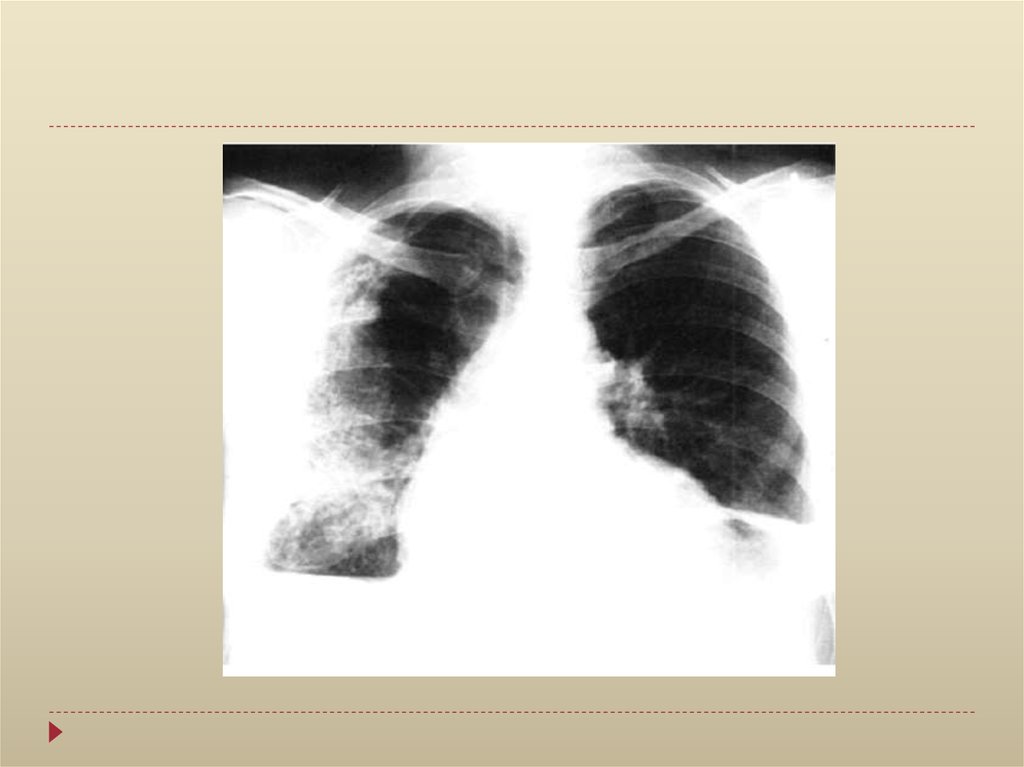

Рентгенологическое исследование:

увеличение тени сердца

сглаживание сердечного контура,

исчезновение “талии” сердца

ослабление пульсации контура тени сердца

треугольная форма тени сердца